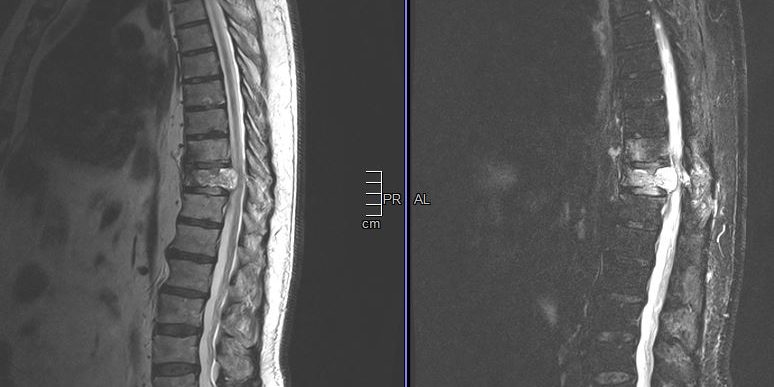

Ασθενής άνδρας 72 ετών με έντονη ραχιαλγία και ιστορικό καρκίνου του πνεύμονα.

Ο απεικονιστικός έλεγχος με μαγνητική και αξονική τομογραφία της σπονδυλικής στήλης ανέδειξε μάζα κυρίως στο σώμα του 10ου θωρακικού σπονδύλου (Θ10) με περιβρογχισμό και πίεση επί του νωτιαίου μυελού. (Σημειώστε και τη διήθηση του Θ9 σπονδύλου, χωρίς οστεόλυση).